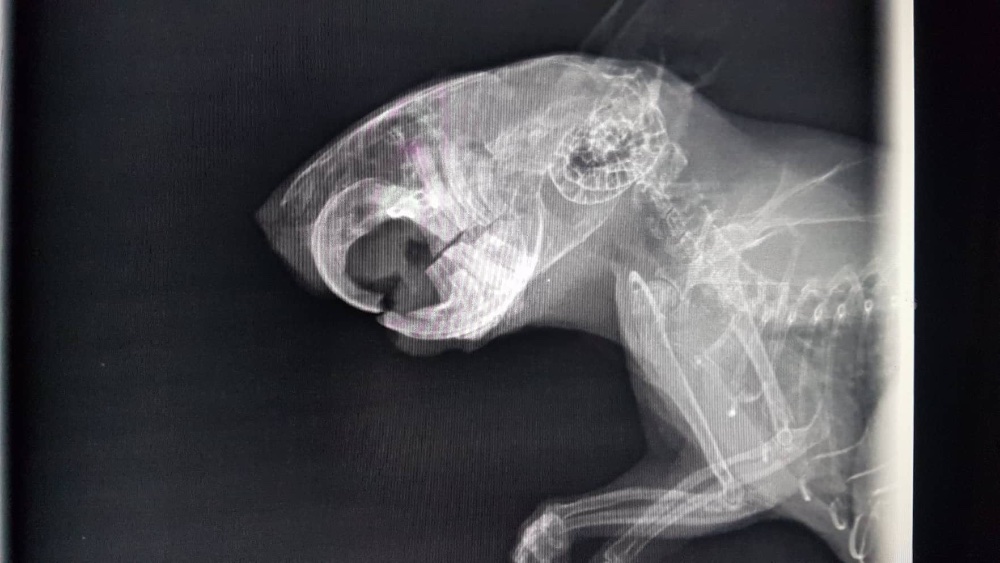

Also ab zum Tierarzt. Sie hat keine Veränderungen feststellen können - auch im Röntgenbild nicht. Er hat aber gefressen, nur eben langsam und eher die weichen Sachen. Nach ein paar Tagen wurden dann auch die unteren Schneidezähne schwarz

Und dann... tja, dann sind irgendwie alle Zähne nacheinander abgebrochen und sind in wunderschönem, gelblichen, gesunden Farbton wieder gekommen. Okay... ich verstehe es nicht, bin aber erstmal zufrieden. Trotzdem isst der blinde Zauberer nur mäßig festes Futter, schlingt aber den Brei. Also wieder mal zum Doc, wieder die Zähne gemacht, ein paar Spitzen geschliffen, aber sonst hat er gute Zähne. Auch das Röntgenbild scheint das zu bestätigen.

Und wenn ich mir sein letztes Röntgenbild so ansehe... irgendwie (jetzt wo man es weiß) sieht es schon da irgendwie anders aus, als hier

- merlin_roentgen.jpg (136.79 KiB) 2444 mal betrachtet